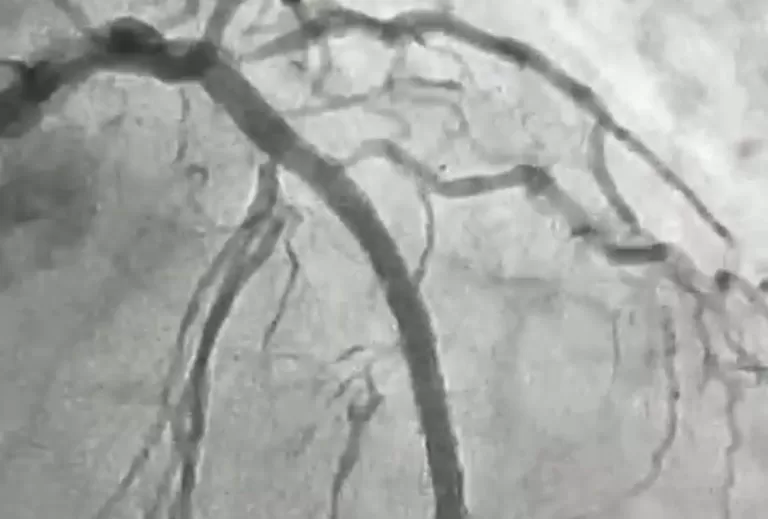

O procedimento foi realizado em uma paciente de 84 anos, moradora de Itaporanga, que apresentava uma lesão grave e altamente calcificada na artéria descendente anterior, considerada a principal artéria do coração. Segundo o cardiologista intervencionista, Jeann Santiago, um dos médicos responsáveis pela realização do procedimento, a condição exigia um tratamento extremamente delicado, com risco elevado, devido à dureza da placa obstrutiva, comparada pelos médicos a uma “pedra” no interior do vaso.

“Para possibilitar a abertura da artéria, a equipe utilizou a aterectomia rotacional, técnica que funciona como uma microfuradeira capaz de desgastar e desobstruir placas de cálcio muito rígidas. Em seguida, com o auxílio do ultrassom intravascular, foi possível medir com precisão a extensão da lesão e determinar o tamanho ideal dos dispositivos a serem implantados. Após a preparação do vaso, foram colocados dois stents farmacológicos, completando o processo de revascularização”, explicou o cardiologista.

O procedimento foi conduzido, também, pelo cardiologista intervencionista Luan Martins, além do apoio de uma equipe multiprofissional. “Foi um procedimento de extrema complexidade, algo que antes só era feito em centros maiores. Conseguimos tratar uma lesão muito calcificada com total segurança e eficácia, utilizando recursos de ponta. É uma conquista para a Hemodinâmica de Patos e, principalmente, para a população do Sertão”, destacou Jeann Santiago.